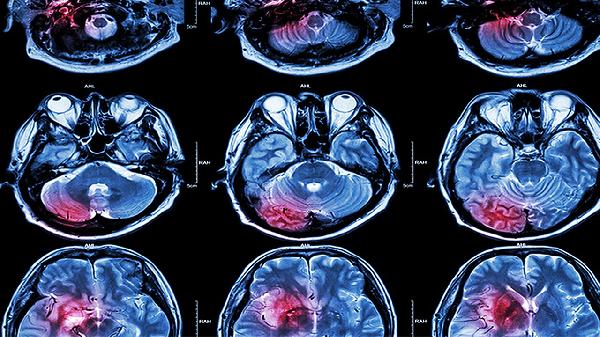

脑梗死护理诊断方法主要有观察意识状态、评估肢体功能、监测生命体征、检查吞咽功能、识别心理状态等。